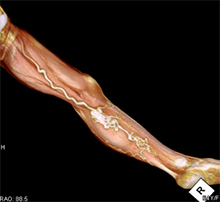

<手術前>両側総腸骨動脈(お腹の中にある足のつけねの動脈)と両側大腿動脈(太ももの動脈)に閉塞、狭窄部位があり、運動障害(間歇性跛行)や皮膚障害(壊死)を引き起こし、車椅子に乗られての入院となりました。

<手術後>右の鎖骨下~腋窩動脈(鎖骨の下から脇の下にかけての動脈)から両側大腿動脈、さらにそこから両側膝窩動脈(膝の裏の動脈)にバイパス手術を施行しました。

運動障害、皮膚障害も改善し、歩いて退院されました。

両側総腸骨動脈狭窄、閉塞

両側大腿動脈狭窄、閉塞